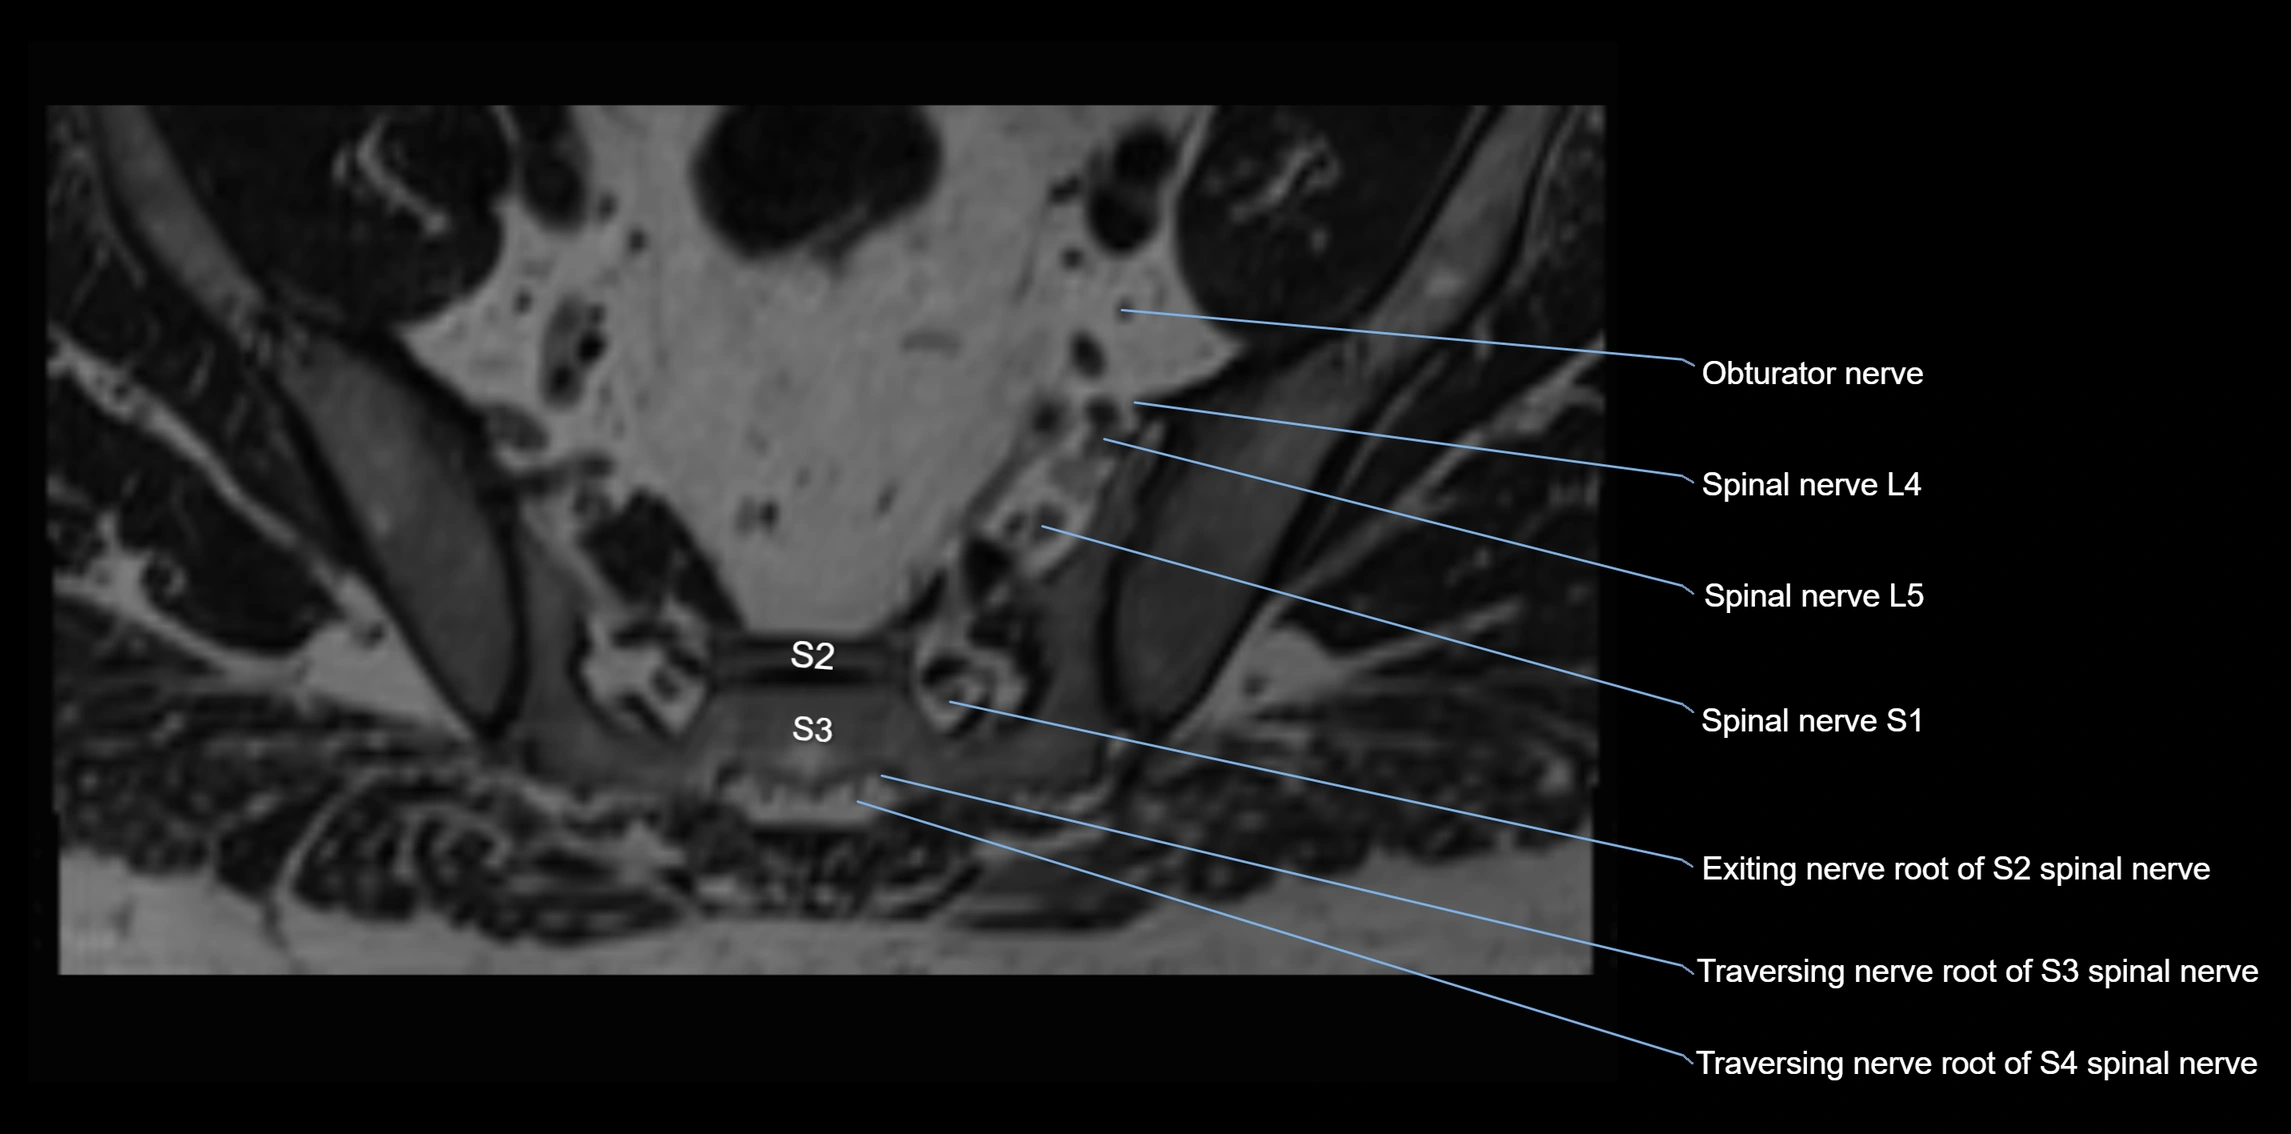

MRI Appearance

T1-weighted images:

• Nerve appears as a very thin low-to-intermediate signal intensity structure

• Surrounded by bright fat, aiding visualization

T2-weighted images:

• Nerve shows intermediate to mildly hyperintense signal compared to muscle

• Pathological involvement appears brighter

STIR (Short Tau Inversion Recovery):

• Normal nerve appears dark

• Inflamed or entrapped nerve appears bright hyperintense

T1 Fat-Sat Post-Contrast:

• Normal nerve enhances minimally

• Pathologic nerve (neuritis, entrapment, tumor infiltration) shows focal or diffuse enhancement

3D T2 SPACE / CISS:

• Nerve appears intermediate to mildly hyperintense compared to muscle

• Surrounded by bright fat or CSF, improving visualization

• Best sequence for mapping small pelvic nerves such as the anococcygeal